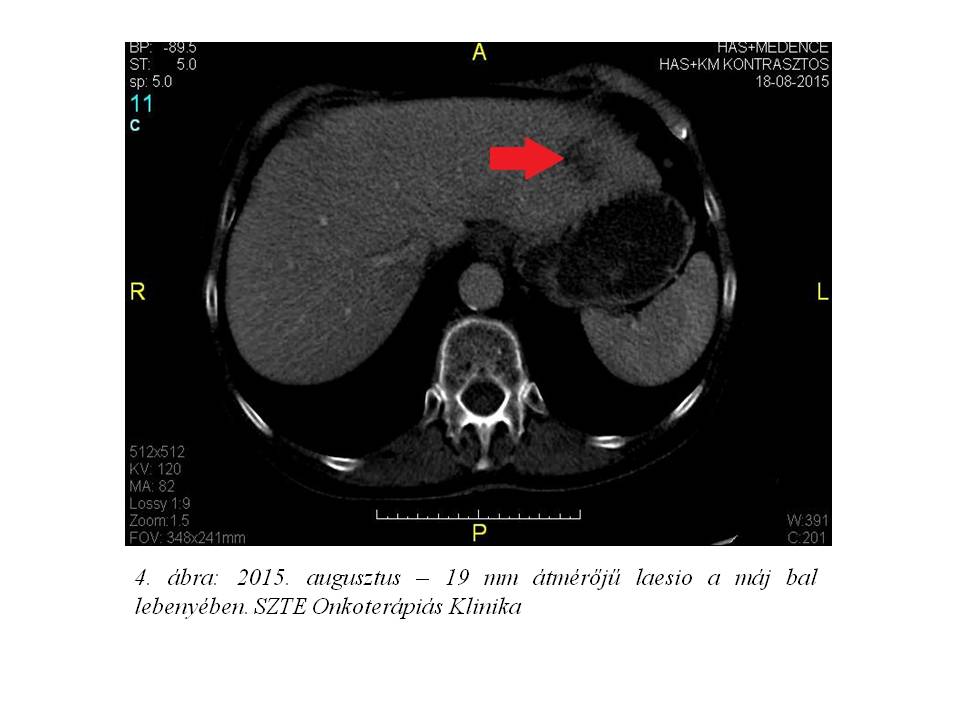

A durg holidayt követően 2015 augusztusában készült friss staging vizsgálatok sajnos a betegség progressioját igazolták. A májban ismételten kóros gócok jelentek meg (4. ábra), melyhez azonban a CA 19-9 szintjének csökkenése társult (122 U/ml). A beteg másodvonalas kezelésének meghatározása folyamatban van.